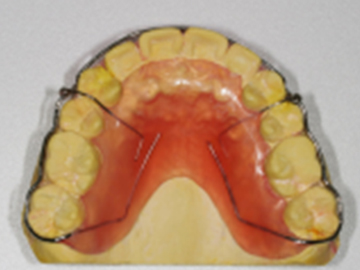

고정식 유지장치를 이용해 교정치료 후 재발을 방지합니다.

가철식 유지장치를 이용해 교정치료 후 재발을 방지합니다.

교정치료 후 일어나는 약간의 재발은 자연스러운 현상 중 하나입니다.

치아와 턱이 생리적으로 가장 편안한 상태를 찾아가면서 일어나기 때문입니다.

하지만, 힘들게 한 교정치료 결과가 다시 예전으로 돌아가는 것은 막아야겠죠!

심다치과에서는 교정치료 후, 위아래 유지장치를 통해 재발이 최소화되고자 합니다.